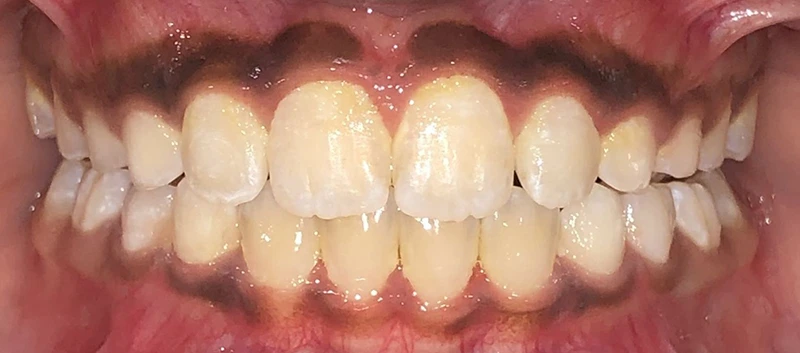

Actual Patient: Alexander

Alexander Before 4 Alexander After 4

Severe “Underbite”, Narrow Jaws, Adult Teeth Not Growing In

Alexander Before 1 Alexander After 1

Front View

Top View

Right & Left Sides

Front View Results

0 Month

6 Month

11 Month